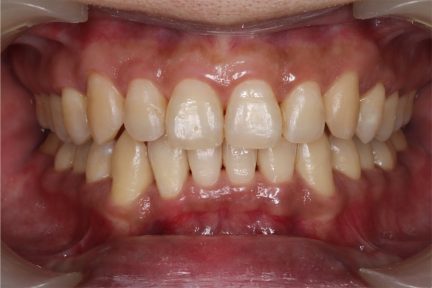

État final

- Il s'agit d'un cas grave de supraclusion.

- L'aligner Invisalign est un excellent système pour résoudre les problèmes de supraclusion sans mettre de turbos d'occlusion sur les dents antérieures, permettant alors au patient de continuer à manger facilement.

- Une ingression étagée pour les dents antérieures inférieures a été utilisée pour assurer une ingression parfaite.